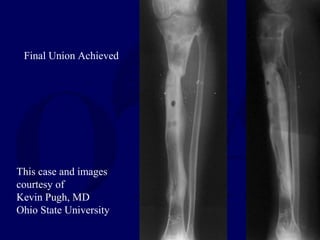

This case and images courtesy of

Kevin Pugh, MD

Ohio State University

Retrograde transport of a

14 cm segment required

2 years in the frame

Patients can weightbear in the frame

while the segment is consolidating and

healing at the docking site

This case and images

courtesy of

Final Union Achieved